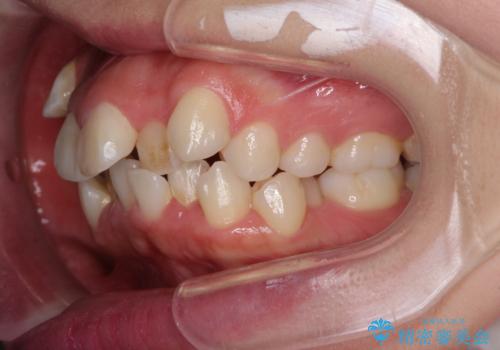

- 前歯の著しい叢生や八重歯を気にして来院された患者様です。

上下の顎がずれており、上下の正中は歯1本分の差がありました。

上下左右の小臼歯4本を抜歯し、極力正中を合わせるように矯正治療を始めていくこととしました。

咬み合わせの乱れが著しく、治療途中で一部反対咬合となってしまいました。